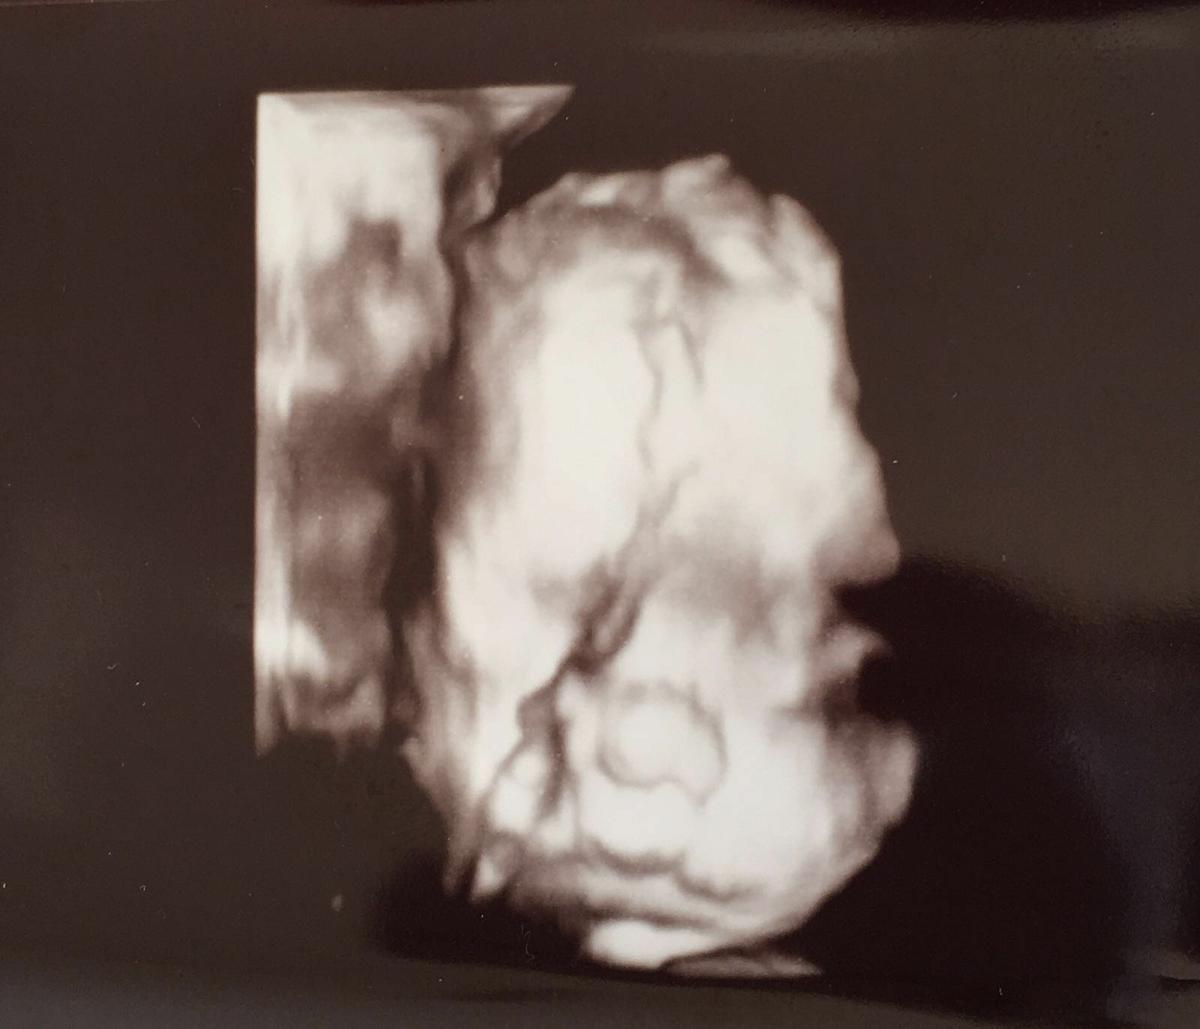

Os voy a enseñar su carita

Parece que esta algo enfadada…jajaja!! Pero ya se le ven las facciones perfectamente, es chatina como sus padres y la boca completamente perfilada.

Es inevitable que se empiecen con los parecidos, que si se parece al padre que si a la madre…ya sabéis la familia paterna tira para el padre y la materna para la madre. Pero lo que yo digo… hay un problema, porque mi chico y yo de pequeños los dos hemos sido parecidos, narices chatas, rubios, lo único que uno tiene los ojos más grandes que el otro.

Y esta última es en 2d, las otras eran ecos en 4d que la verdad es que es una pasada…